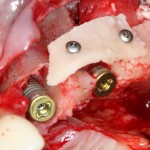

Итак, мы удаляем клык, по шаблону устанавливаем импланты, строим «каркас» будущего альвеолярного гребня в области пятерки:

Для синуслифтинга мы используем Geistlich Bio-Oss, который пригодился нам как для остеопластики (наполнения построенного «каркаса»), так и для аугментации лунки:

Проводя остеопластику, мы не забываем о «факторах успеха остеопластических операций«, в частности о факторе #3. Поэтому, несмотря на то, что «классикой» немедленной имплантации является установка формирователя десны, мы перекрываем лунку клыка барьерной мембраной и ушиваем ее наглухо: